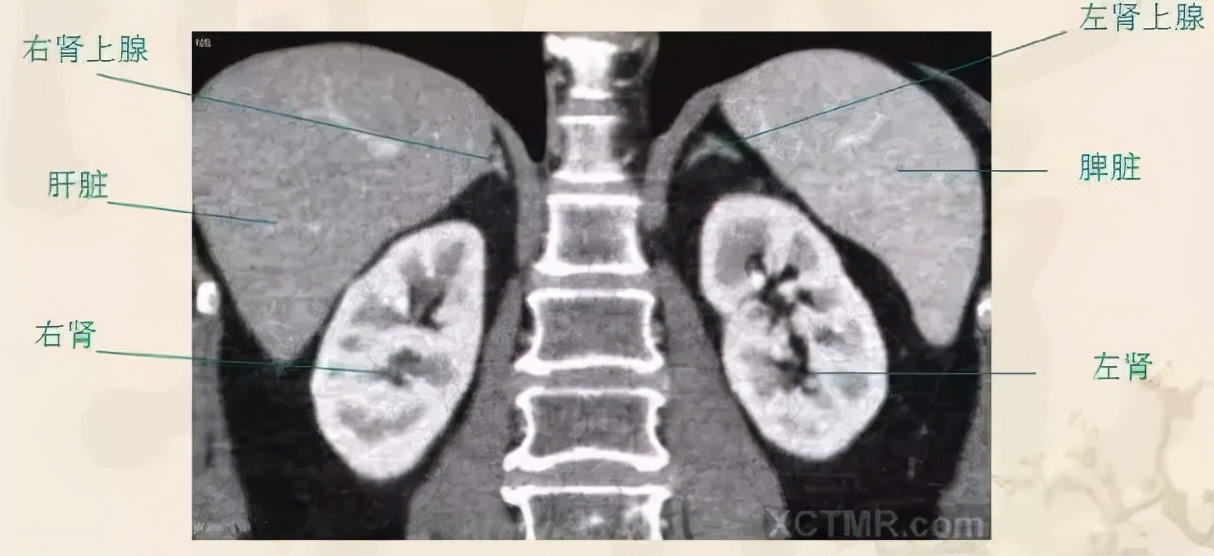

正常肾上腺冠状位CT多平面重建(MPR)